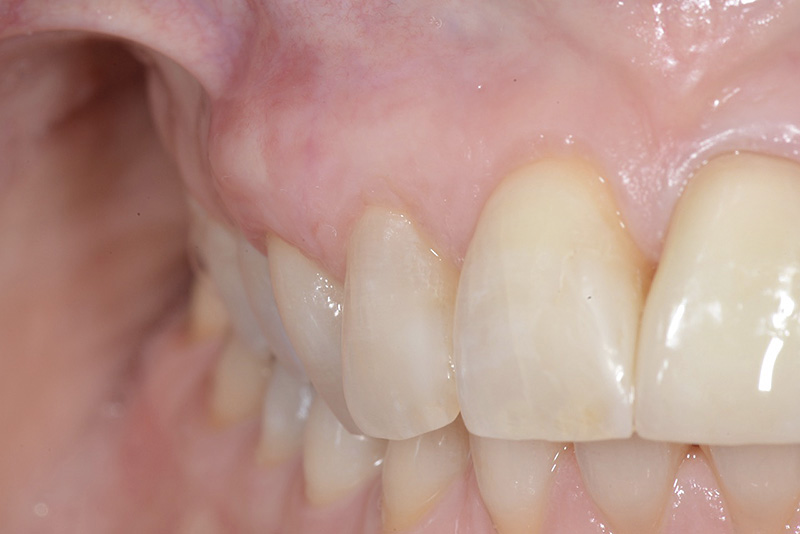

PREMESSA: in seguito all’estrazione dell’incisivo laterale superiore di destra, resasi necessaria per cause batteriche, si decide di affrontare il caso con il posizionamento di un impianto in sostituzione dell’elemento mancante dopo guarigione del sito infetto. Con tecniche rigenerative sia dei tessuti ossei mancanti a causa dell’infezione pregressa, sia dei tessuti gengivali che appaiono inizialmente troppo spostati in alto, si ripristina una corretta morfologia delle parabole (contorni) gengivali e delle papille interdentali (triangoli di gengiva tra due denti vicini).

Vengono utilizzati 2 tipi di provvisori: il primo, cementato ai denti vicini, viene utilizzato dal momento dell’estrazione del dente fino ad impianto osteointegrato (circa 6 mesi); il secondo, avvitato direttamente all’impianto, ha una funzione di prova estetica ma soprattutto di guida per la maturazione dei tessuti gengivali peri-implantari portandoli verso la maturazione completa prima di posizionare la corona finale in disilicato di litio.